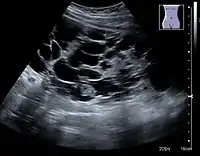

Renal ultrasonography of a simple renal cyst with posterior enhancement.

Advanced polycystic kidney disease with multiple cysts.[12]